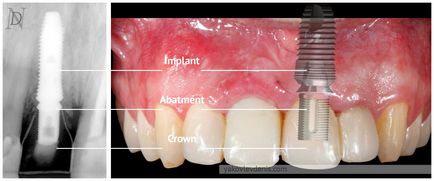

A fogászati implantátum három fő részből áll:

• közvetlenül az implantátum magát - egy mesterséges titán root)

• Felépítmény - átmeneti darab az implantátum és a mesterséges koronát,

• korona

A variáns közvetlenül rögzítése a korona az implantátum (a felfekvő koronák oszthatatlan platform csavaros rögzítést).